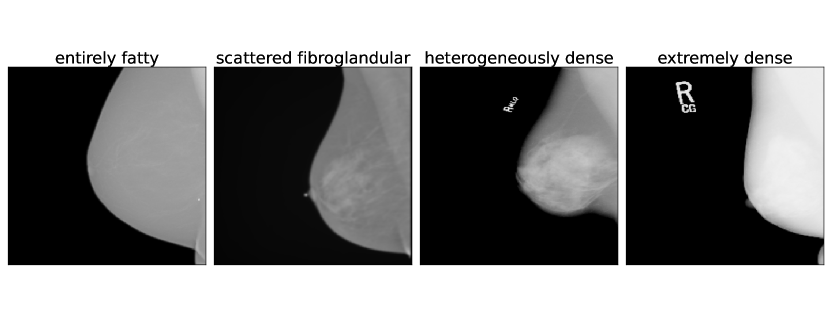

Breast density was assessed according to BI-RADS criteria into one of four categories: “entirely fatty”, “scattered fibroglandular”, “heterogeneously dense”, or “extremely dense” (Liberman & Menell, 2002).